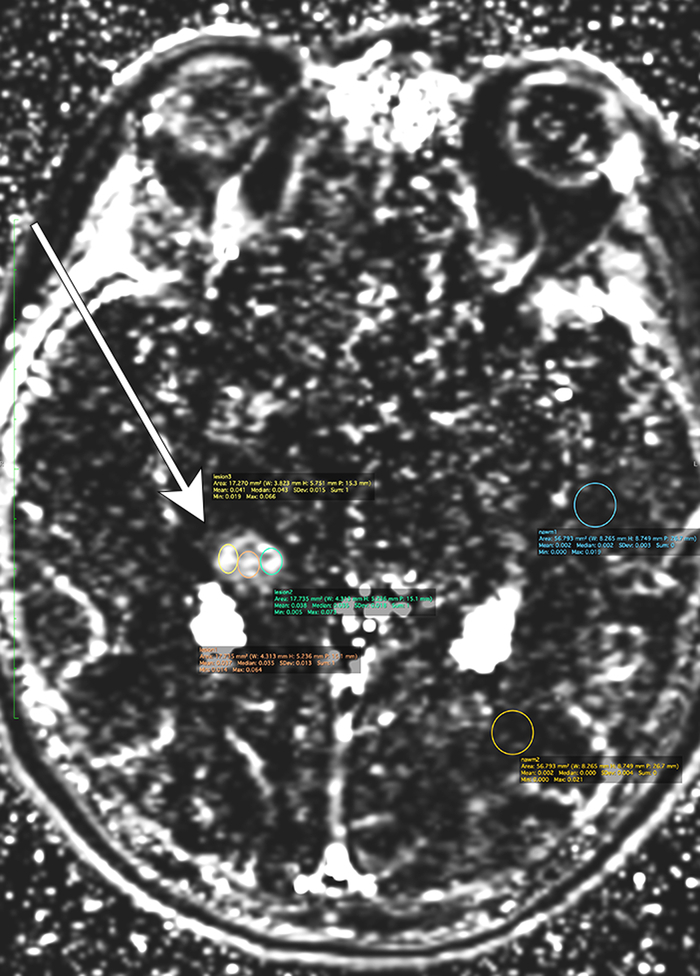

Methods: We identified 110 patients with HGG treated with surgery and chemoradiation who underwent DCE-MRI to further interrogate areas of new/increasing enhancement. All patients had confirmatory surgery/biopsy with pathology-confirmed progression or pseudoprogression. Scans were performed at 3T and analyzed using nordicICE. The MCA, SSS, and Parker models are three standardized processing methodologies used to create k trans maps, a parameter that quantifies BBB permeability. Three equal regions of interest were placed at sites of peak contrast enhancement within each lesion. Data from each method was processed for mean and maximum k trans . We conducted several rounds of analysis and finalized a strategy on penalized support vector machines based on engineered features with bootstrap sampling.